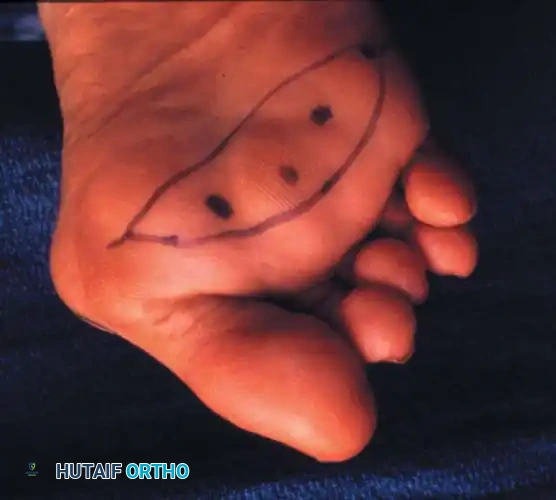

- Approach: Two dorsal longitudinal incisions are typically utilized (one centered between the 2nd and 3rd rays, and one between the 4th and 5th rays) to access all lesser MTP joints while preserving dorsal skin bridges. Alternatively, a transverse plantar approach can be used if severe plantar callosities require excision.

Intraoperative view demonstrating the exposure and resection of the lesser metatarsal heads to decompress the forefoot and allow reduction of the dislocated digits.